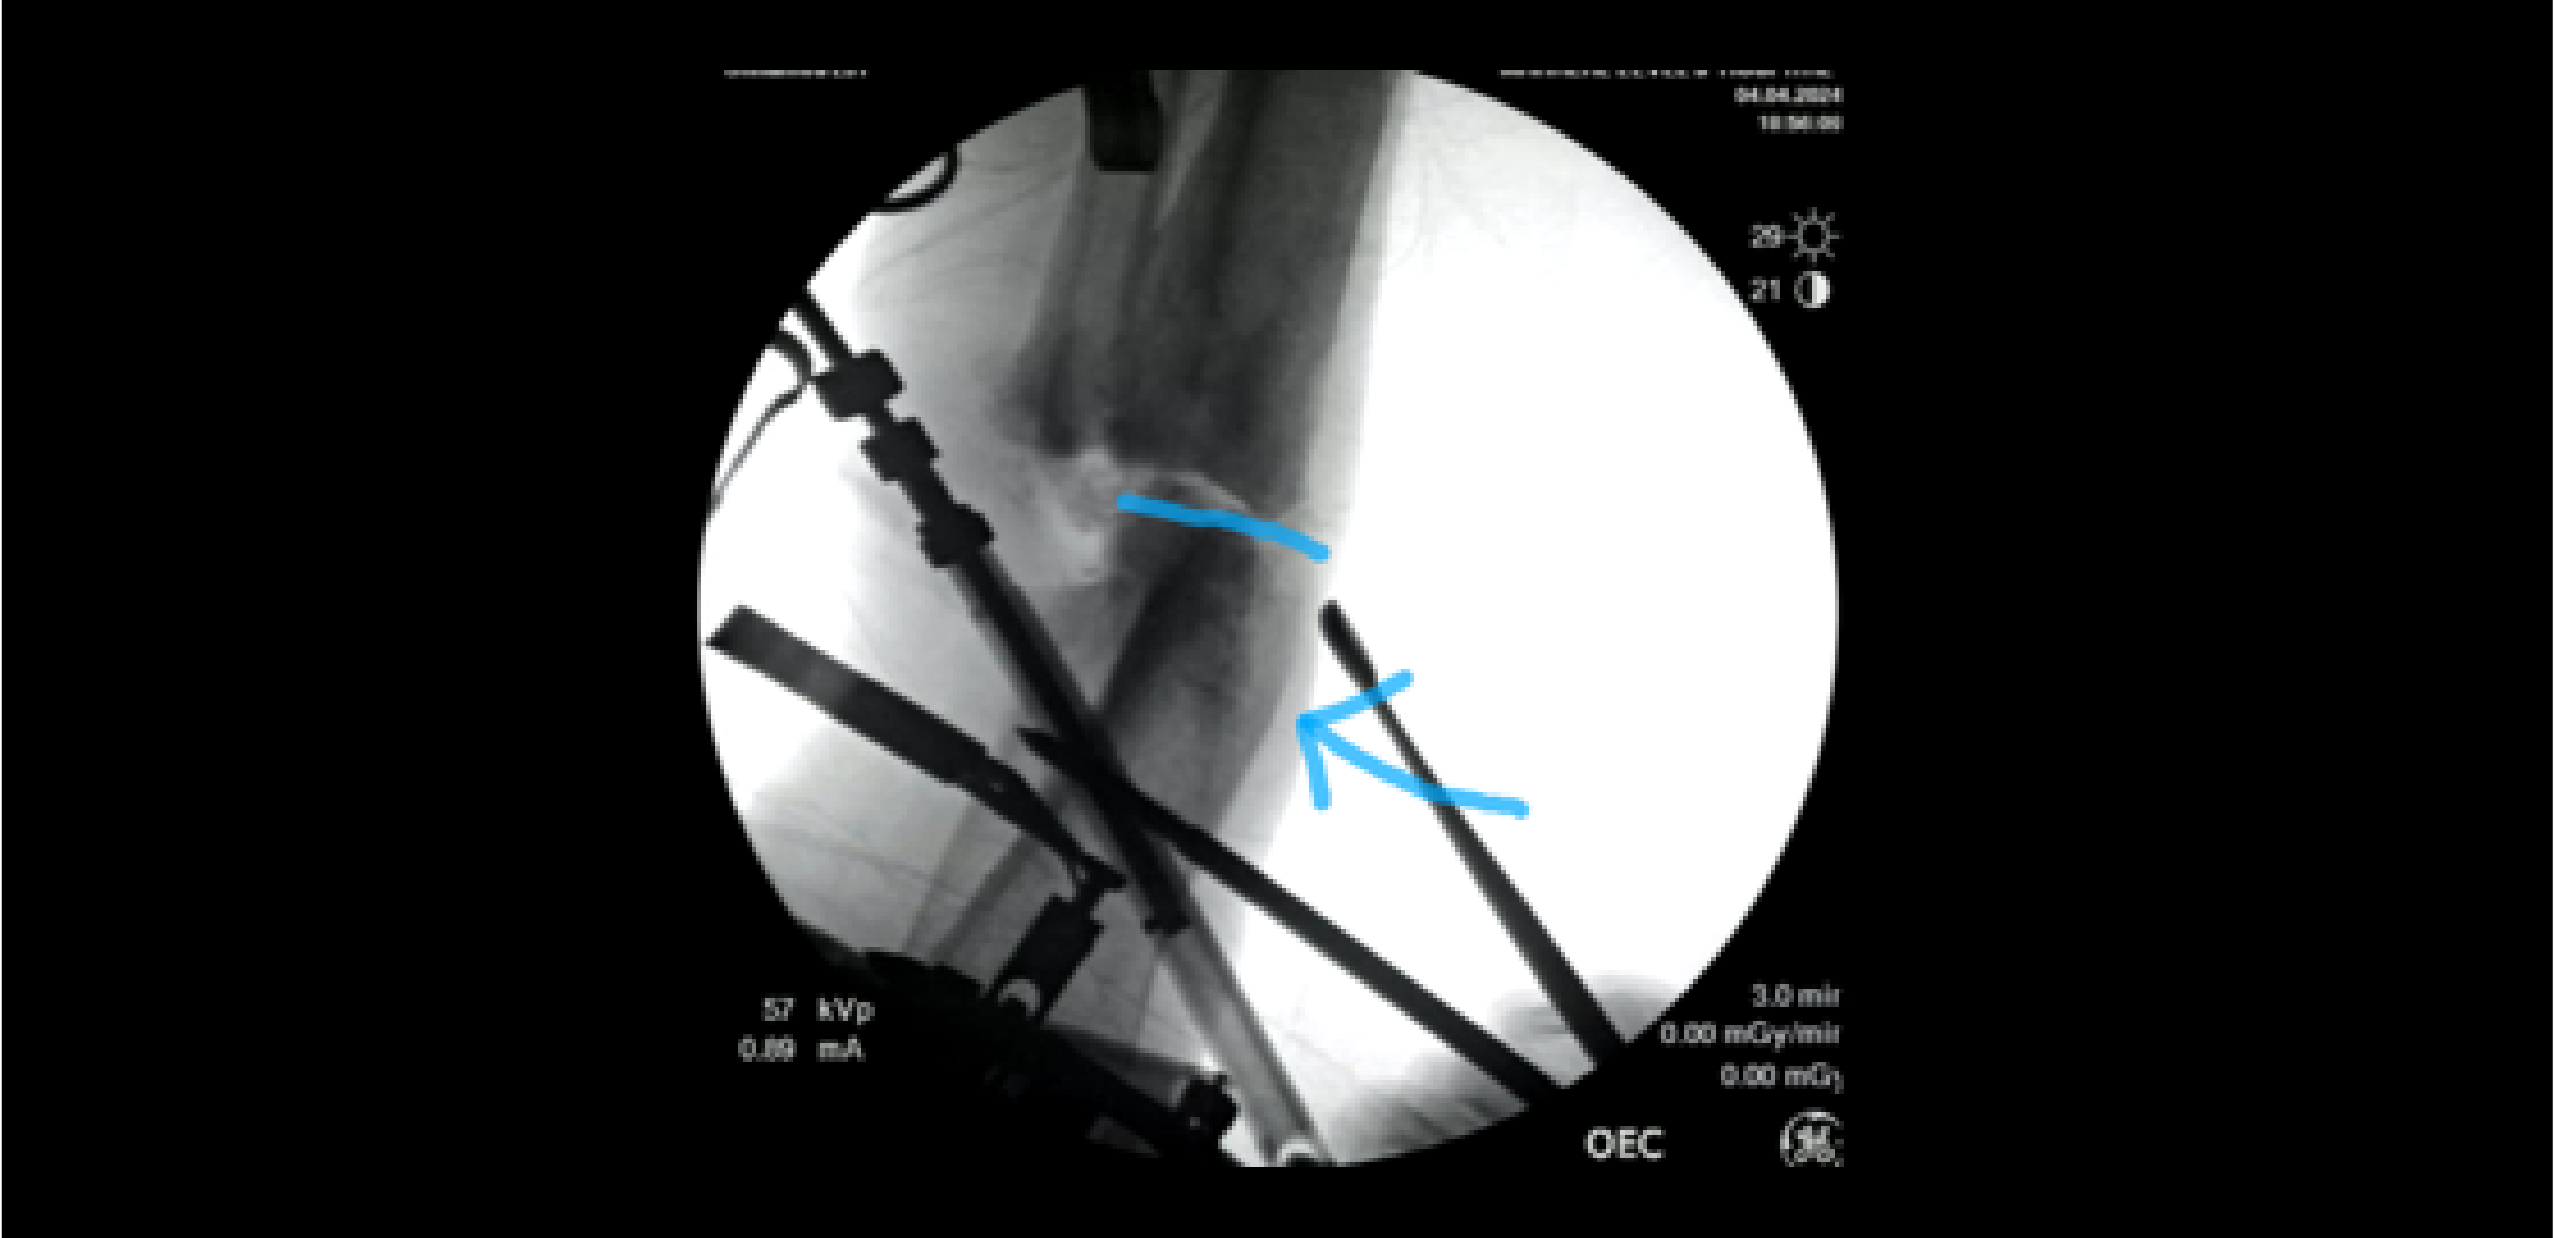

An indication of a bone resection is being performed to prepare an external fixator (ex-fix) docking site. This view is provided by mentee Dr. Daniel Scuito at Samburu County Teaching and Referral Hospital in Maralal, Kenya.

The view on the left shows a preliminary assessment of a correction procedure for the distal tibia. This stage is crucial for ensuring proper alignment and stability before further intervention.